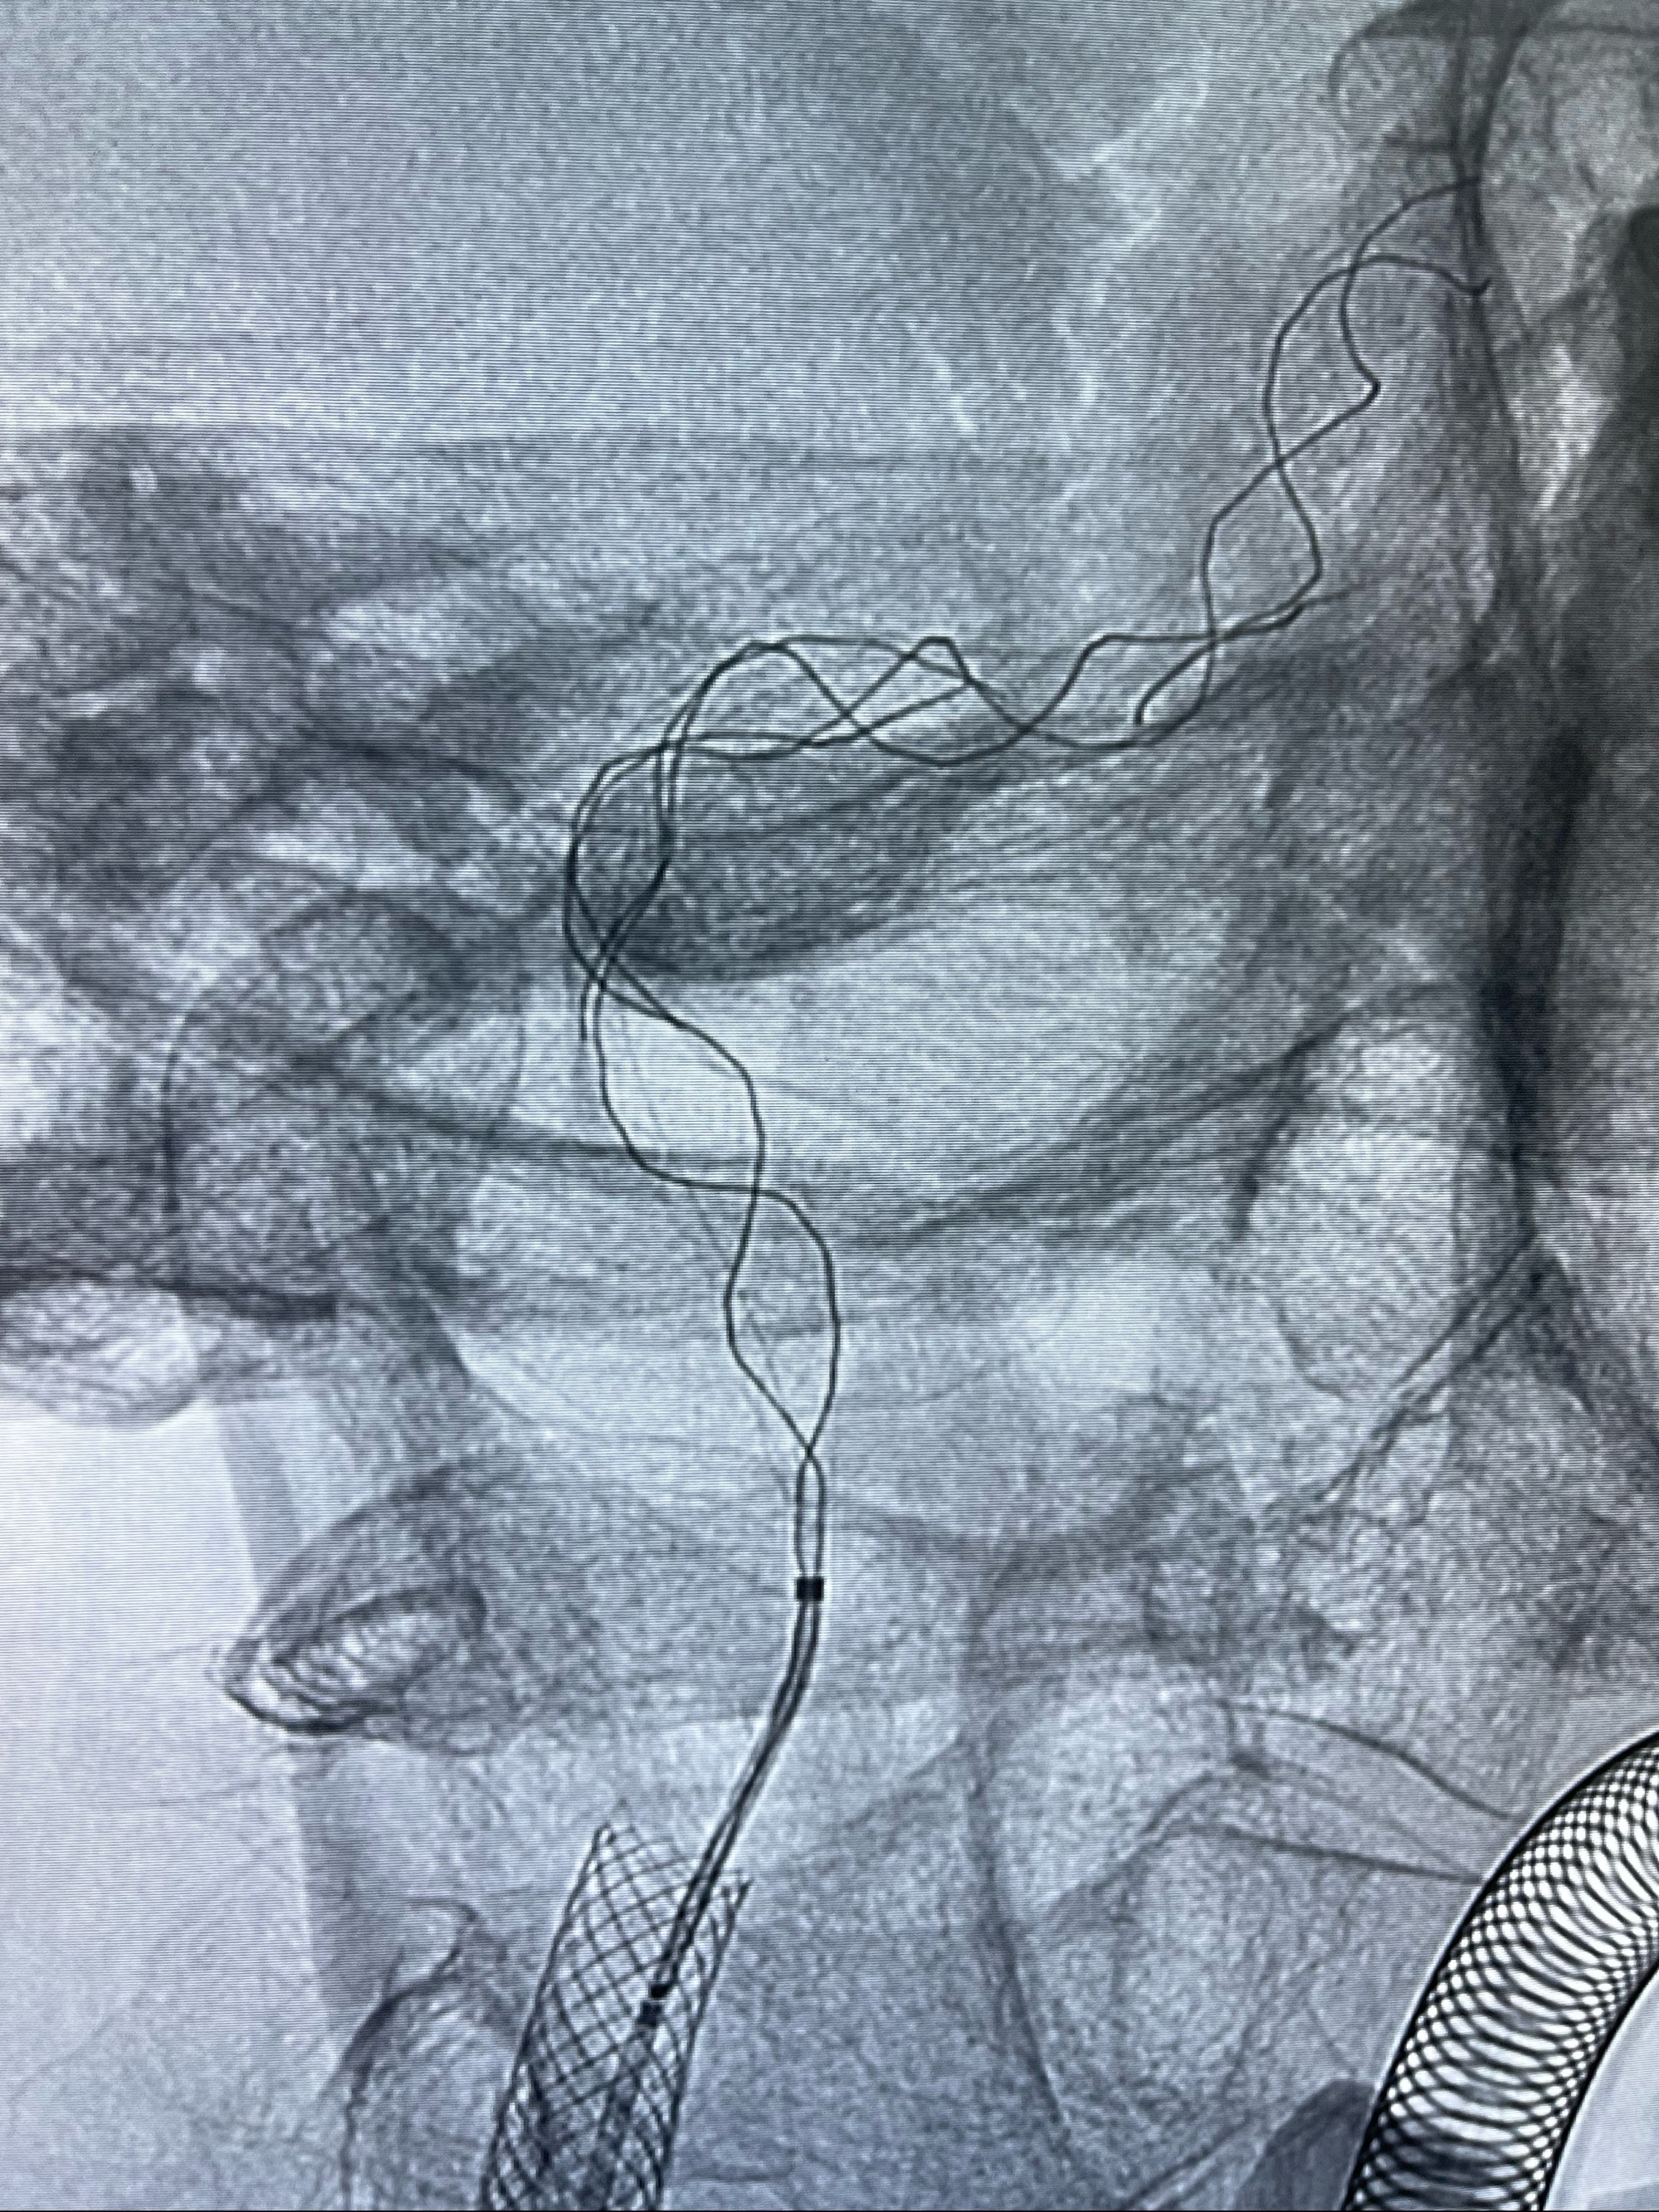

双抗准备后于2023-07-13在全麻下行右侧颈内动脉功能保护

088NeuroMAX100cm长鞘在125cmMPA及黑泥鳅导丝引导下超选择性插入右侧颈内动脉支架内

经导引导管造影显示支架远端颈内动脉不规则狭窄伴局部充盈缺损,同时行全身肝素化5ml

路径图下4-20mm球囊在导丝引导下超选择性至狭窄段,以6-8个大气压扩张,持续30s

泄除球囊造影显示局部管腔扩张佳

后移球囊至颈段狭窄段,以8-12个大气压扩张,持续30s后泄除球囊

即刻造影显示狭窄扩张佳

重新行“路径图”,支架导管在微导丝引导下超选择性插入至右侧颈内动脉眼段,4.5-50mmLeo支架释放,远心端位于海绵窦段,近心端位于岩骨段狭窄段以近

即刻造影显示支架贴壁佳

路径图下,5.5-50mmLeo支架导管在微导丝引导下超选择性插入远段Leo支架内

两枚支架部分重叠

多次确认支架位置及打开贴壁情况

支架完全打开,近心端位于原颈动脉支架远心端内